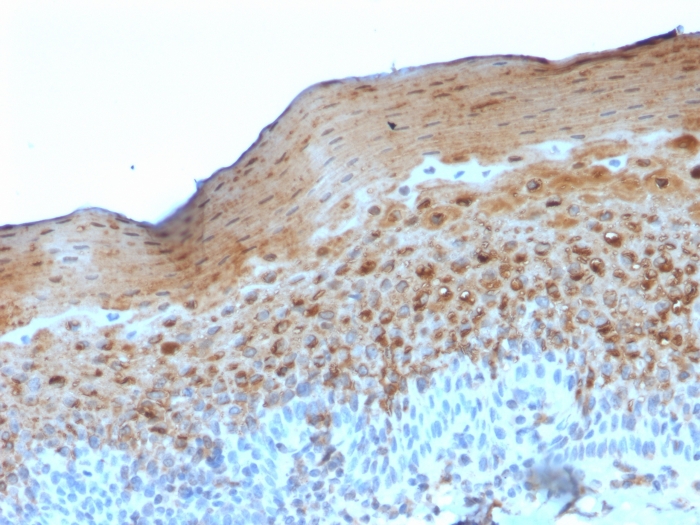

Formalin-fixed, paraffin-embedded human Tonsil stained with Involucrin Mouse Monoclonal Antibody (SY5).

It recognizes a protein of 66kDa-170kDa, identified as involucrin. In Western blotting of cultured human keratinocytes, this MAb reacts with a 120kDa protein. It stains the involucrin in a variety of sizes: 170kDa in MCF-7 cells, a doublet of ~115kDa and 150kDa in gorilla and owl monkey, 66kDa in dog, and a doublet of 105kDa in pig. Its epitope maps between codon 421-568 of human involucrin. Involucrin is expressed in a range of stratified squamous epithelia, including the cornea, which lacks a distinct cornified layer. In normal epidermis, it is first expressed in the upper spinous layers, and in keratinocyte cultures, all cells that have left the basal layer express it. Involucrin expression is altered in pathological conditions: in psoriasis and other benign epidermal hyperplasias, involucrin expression begins closer to the basal layer than normal; expression is abnormal in squamous cell carcinomas and premalignant lesions, and is reduced in severe dysplasias of the larynx and cervix.